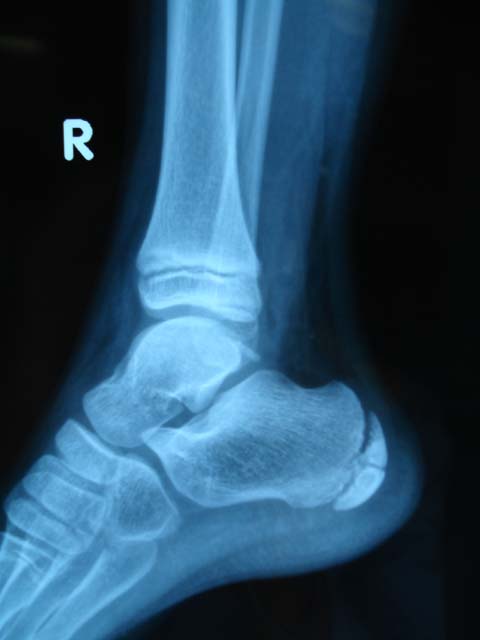

女,9岁。下楼是扭伤脚部。大家看看跟骨骨骺正常吗?有疲劳性骨折么?其骨化中心只有1个吗?

未见异常,跟骨化骨中心有-----两个。

骨骺与骨折的鉴别应从多方面综合考虑:

1、有否外伤史;

2、透亮线是圆钝(骨骺)或锐利(骨折线);

3、有否错位(有错位的是骨折)...

正常,正常跟骨骨骺骨化中心可\"节裂\",密度较高

支持两个骨化中心。

两个骨化中心

支持跟骨两个骨化中心     边缘较光滑      必要时可摄片双侧对比

疲劳性骨折多见于运动员、芭蕾舞演员、士兵   常骨折发生部位为跖骨   胫骨

正常骨骺,必要时加照对侧位对比,疲劳性骨折多见于足第二跖骨。